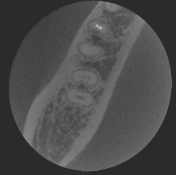

過剰歯

-

70μm(Voxel Size)高精細モード搭載

End、根尖、破析、分岐部病変など精細読影をサポートします。

CT撮影時、Free FOVで撮影に必要な領域を絞り込み、

的確に高解像度70μmの世界トップレベルのCT画像を再現します。-